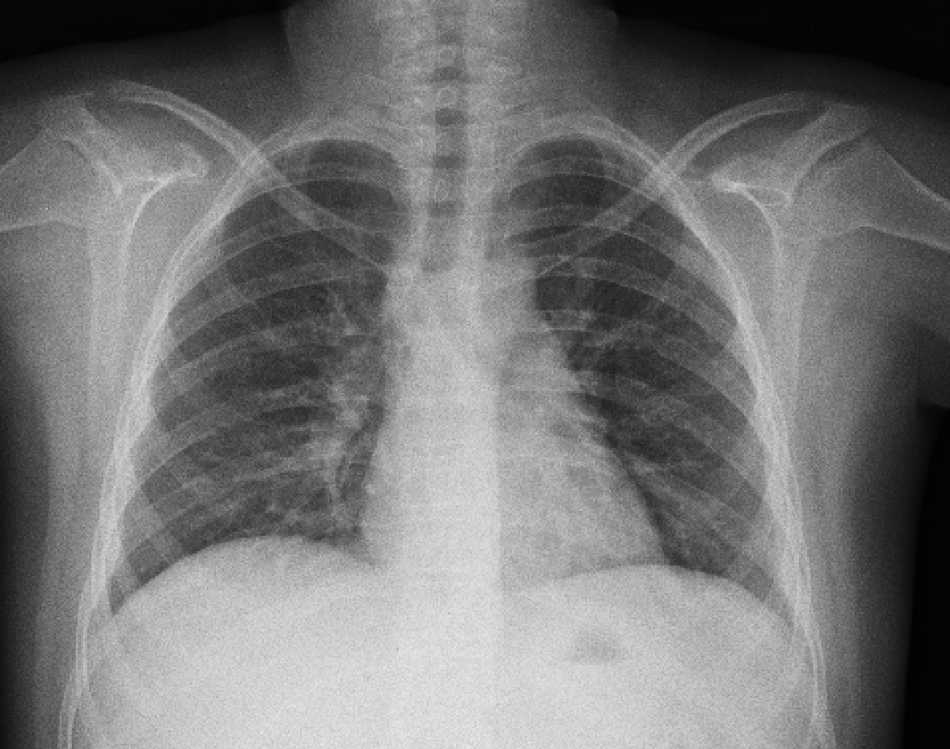

La radiografía de tórax inicial mostró infiltrado micronodular y reticular difuso con adenopatías hiliares bilaterales (Fig. 1).

A su ingreso se detectó insuficiencia respiratoria crónica tipo I, sin repercusión cardiovascular, con hipoxemia, normocapnia e hiperlactatemia. La radiografía de tórax mostró infiltrado micronodular y reticular difuso con adenopatías hiliares bilaterales, concordante con el Estadio II de la clasificación de la American Thoracic Society para sarcoidosis torácica. Así mismo, la espirometría y la pletismografía reportaron una disminución de la relación VEF1/FVC, compatible con una neumopatía de patrón restrictivo leve como se ha descrito en las dos primeras etapas de la sarcoidosis pulmonar, que se normalizó después del tratamiento con prednisona.